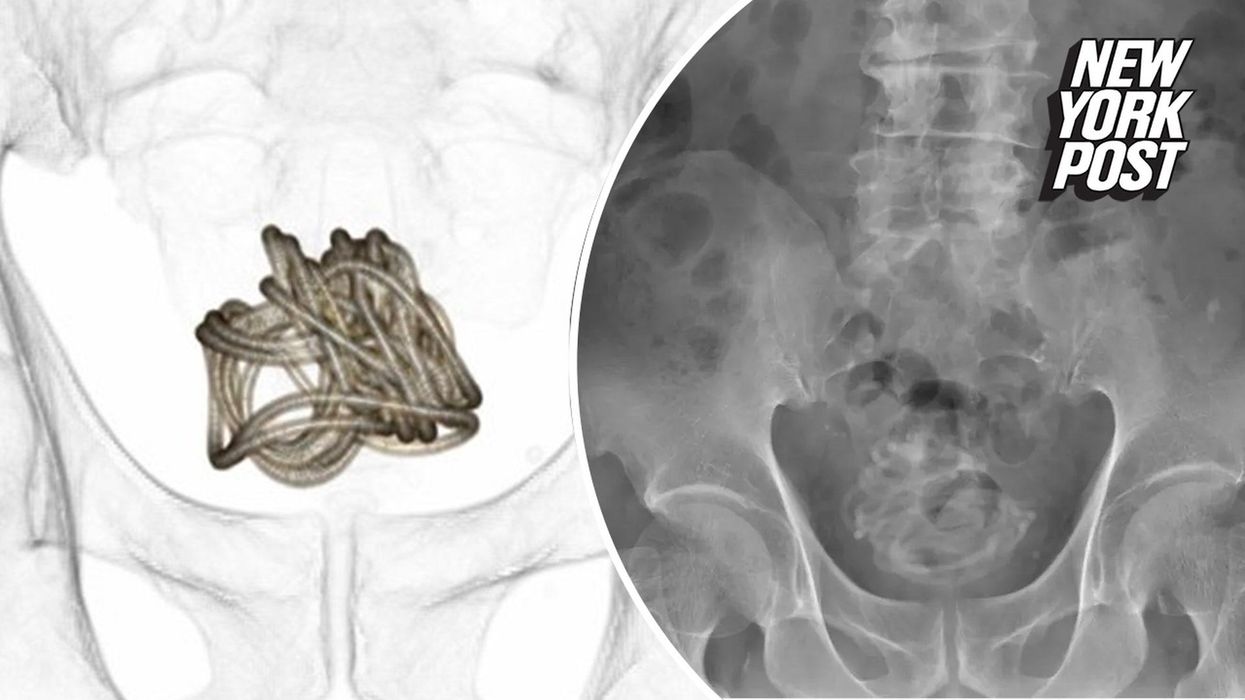

After various scans, doctors discovered "a large object accompanied by acoustic shadows", which they later learnt to be "an intricately entangled jump rope in the bladder".

Once doctors established the foreign object, they went on to remove the rope after deeming endoscopic surgery unsuitable.

Given the large length of the rope and its placement in the bladder, the extraction was unsurprisingly difficult.

"Traditionally, grasping forceps and retrieval baskets are used to remove foreign bodies," said Professor Toshiki Kijima, co-author of the study. "However, wires inserted into the bladder usually curl up as the bladder contracts; therefore, special consideration is required for wire-like foreign bodies."